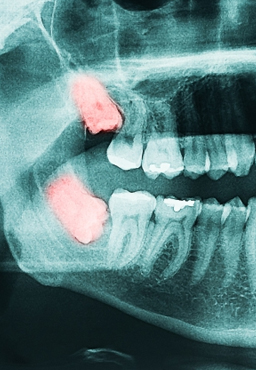

Xray of root canal work